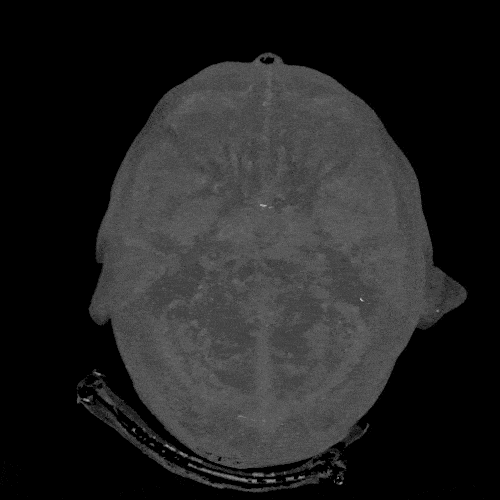

Among all other flash drives, our brain is the largest you can ever find in the world.

Well, till date we have not known how much our memory can store. Well, according to the estimations made, it was out that memory of our brain is 2.5 million GB. And it will load around 300 years of the video. Well, in initial the peak development of the mind is at the age of twenty-five years. But it also decreases after you attain the age of fifty years. It can get a cure if you will on training yourself with your memory.